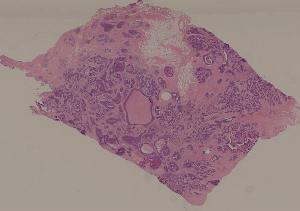

80.乳腺浸润性导管癌

低倍视野